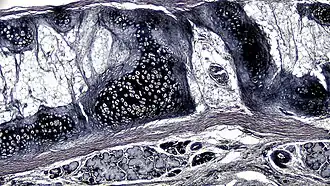

![]() Corte transversal de cartilagem elástica de mamífero | |

A cartilagem elástica é histologicamente semelhante à cartilagem hialina, mas contém muitas fibras elásticas amarelas dispostas em uma matriz sólida. Essas fibras formam feixes que aparecem escuros sob um microscópio. As fibras elásticas exigem coloração especial, pois quando coradas com hematoxilina e eosina (H&E) aparecem iguais à cartilagem hialina.[3] São usados corantes de Verhoeff van Geison (dando às fibras elásticas uma cor preta), mas corantes de fucsina aldeída, corantes elásticos de Weigert e corantes de orceína também funcionam.[3] Essas fibras conferem à cartilagem elástica uma grande flexibilidade, de modo que é capaz de suportar flexões repetidas. Da mesma forma que na hialina, um ou múltiplos condrócitos ficam entre os espaços (ou lacunas) nas fibras.[2] Os condrócitos representam apenas 2% do volume do tecido.[2] Os condrócitos e a matriz extracelular estão contidos em uma camada externa chamada pericôndrio[2] (que é uma camada de tecido conjuntivo denso não modelado que envolve a cartilagem independente da articulação).[3] É encontrada na epiglote (parte da laringe) e nos pavilhões auriculares (a parte externa da orelha de muitos mamíferos). As fibras de elastina coram em roxo escuro/preto com o corante de Verhoeff.